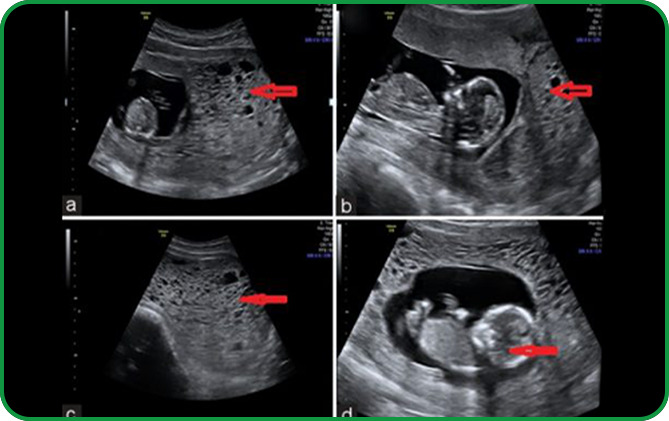

IX. ĐA ỐI, THIỂU ỐI

Lượng nước ối cuối thai kỳ thường vào khoảng 500ml, nếu từ 1500ml trở nên thì gọi là đa ối, nếu dưới 100ml thì gọi là thiểu ối. Trên lâm sàng dựa vào chỉ số ối khi siêu âm (ở 4 góc):

+ Nếu ≤ 5cm hay chỗ góc sâu nhất ≤ 2 cm: Thiểu ối

+ Nếu ≥ 25cm hay chỗ góc sâu nhất ≥ 8 cm: Đa ối

Nguyên nhân có thể do mẹ bị bệnh đái tháo đường, đái tháo đường thai kỳ hay nhiễm trùng; cũng có thể do suy giảm chức năng của nhau thai, dị dạng thai…Mọi trường hợp đa ối, thiểu ối đều cần được theo dõi chặt chẽ và xử trí tuân theo y lệnh của bác sĩ chuyên khoa.

Nước ối

Lượng nước ối trong thai kỳ